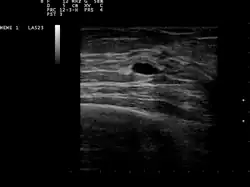

| Ultrasound scan showing a small cyst in the breast | |

The cystic nature of a breast lump can be confirmed by ultrasound examination, aspiration[6] (removal of contents with needle), or mammogram. Ultrasound can also show if the cyst contains solid nodules, a sign that the lesion may be pre-cancerous or cancerous. Examination by a cytopathologist of the fluid aspirated from the cyst may also help with this diagnosis. In particular, it should be sent to a laboratory for testing if it is blood-stained.

Patients suspected of breast cysts will normally be given a diagnosing mammogram, although they are not suspected of cancer. This type of mammogram provides the doctor with the possibility of performing a breast ultrasound at the same time and this is the reason why they are often preferred over the screening mammograms. Breast ultrasound is considered the best option when diagnosing breast cysts because it is 95 to 100% accurate, it provides a clear image on the cyst's appearance (simple or complex) and it may also distinguish between solid lumps and fluid-filled cysts, which a mammogram cannot do.[7] Breast ultrasounds are performed with the help of a handheld medical instrument which is placed on the skin, after a special type of fluid has been applied on it. The instruments picks up the echo resulted from the sound waves it sends to the breast. These echoes are transmitted to a computer which translates it into a picture.